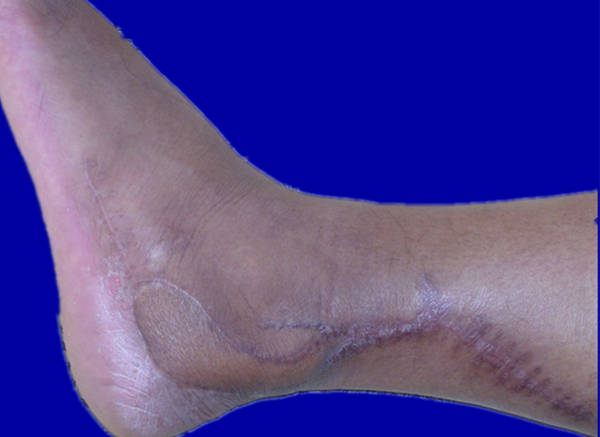

[组织瓣] 改良的外踝后穿支皮瓣修复跟骨骨折术后的皮肤缺损

外踝上2、3cm,具体按多普勒测定的位置